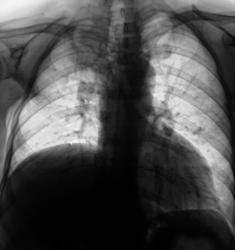

Два года тому поциентке произведена мастэктомия по поводу рака молочной железы. Направлена врачом онкологом (из области) для рентгенографии органов грудной полости. Произведено исследование.

Картина новообразования справа на верхушке, периферического, отсутствие переднего фрагмента 4 ребра справа, релаксация или приподнятость правого купола диафрагмы. Если при рентгеноскопии наличствует парадоксальная подвижность диафрагмы - парез диафрагмального нерва - мета в средостение, если нет - УЗИ печени - искать причину приподнятости купола там.

Как Вам второй вариант: после мастэктомии часто проводят лучевую терапию на над-подключичные л/узлы на стороне опухоли (в данном случае справа), естественно в поле облучения попадает в/доля легкого, где развивается сначала пневмонит, затем фиброз, возможен цирроз. Эти изменения очень вариабельны и зависят от индивидуальной чувствительности. На снимке, кстати, правый корень подтянут вверх, трахея подтянута вправо, в/доля уменьшена в объеме и неравномерно уплотнена. С чего бы этому быть при периферическом образовании? Касательно переднего отрезка 4 ребра справа - он действительно четко не прослеживается, но прозрачность легочного фона в этой зоне повышена, думаю, что снимок на этом участке "перебит" из-за того, что нет молочной железы. Рекомендую уточнить анамнез на предмет лучевой терапии, поднять снимки из архива, если нет такой возможности или остаются сомнения - направить на КТ. На передний отрезок 4 ребра справа требуется сделать прицеленый снимок.

Мне нечего Вам возразить. Два сеанса рентгенотератии уже были.

На мой взгляд, скорее всего здесь имеет место постлучевой фиброз в верхней доле справа с уменьшением объема части легкого. Но для исключения новообразования я бы порекомендовал пройти КТ. Рисковать не стоит.

Затенение в S1, не похоже на перферический рак т.к. последнее всё таки узловое образование.Трахея перетянута вправо- скорее это постлучевой фиброз ( хотя картина несколько необычная, т.к. как правило,при лучевом фиброзе тени тяжистого характера).Нужно КТ( в4 ребре патология).